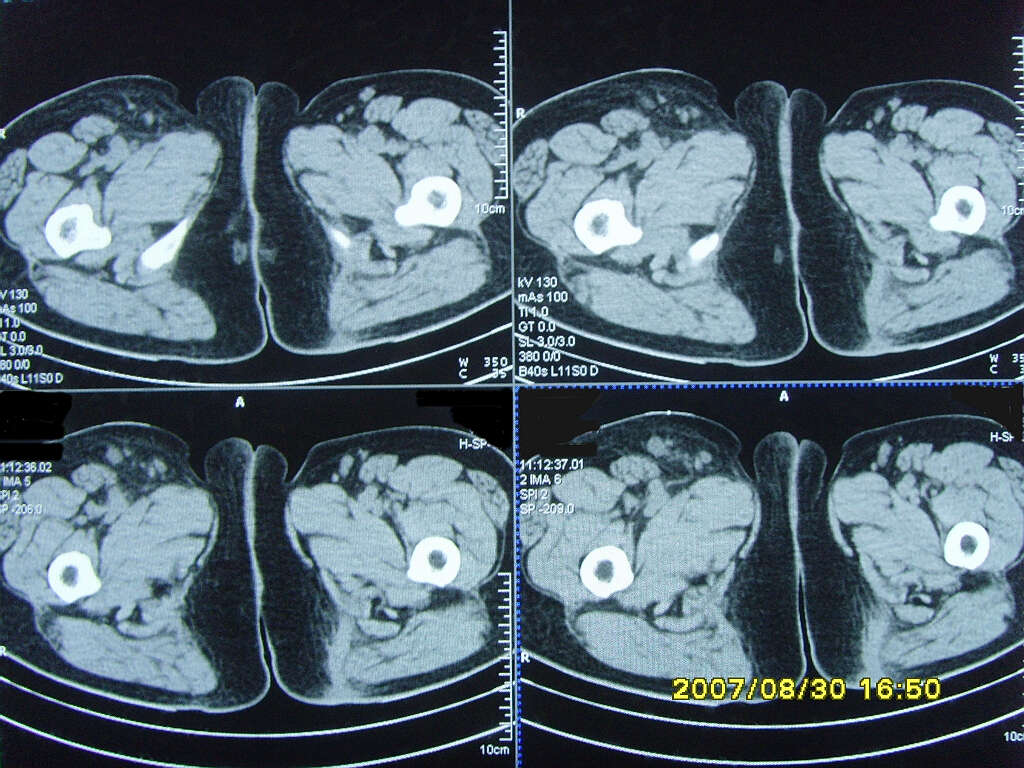

以下是引用zjzjr在2007-9-11 22:21:00的发言:[br]右侧股骨上段前部皮下可见不椭圆形软组织密度影,增强呈环形强化,周围皮下脂肪混浊,考虑感染性病变,不知临床症状如何.